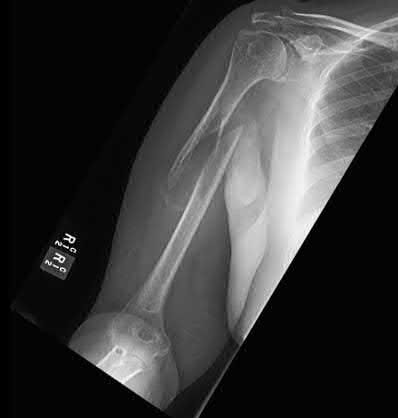

A 15-year-old boy presents with a permeative lytic lesion in the femoral diaphysis with aggressive periosteal reaction ('onion skinning'). Biopsy reveals uniform small round blue cells. Cytogenetic analysis of this tumor will most likely demonstrate which of the following translocations?

Explanation

The clinical and radiographic description is classic for Ewing sarcoma. The characteristic cytogenetic abnormality is a balanced translocation t(11;22)(q24;q12), which fuses the EWS gene on chromosome 22 with the FLI1 gene on chromosome 11. This is seen in approximately 85-90% of Ewing sarcomas. t(9;22) is the Philadelphia chromosome (CML), t(X;18) is seen in synovial sarcoma, t(2;13) in alveolar rhabdomyosarcoma, and t(12;16) in myxoid liposarcoma.